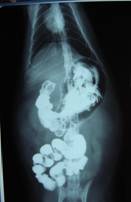

異物を誤食した可能性もあり、バリウム造影を行う。

レントゲンにて明らかに異常な陰影が描出される。